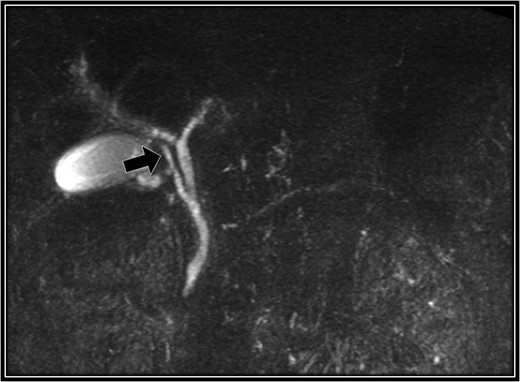

The patient was placed in supine position. Initially, intracorporeal procedures were performed in the laparoscopic view through four trocars (one 12-mm port and three 5-mm ports). We considered using intraoperative cholangiography to explore the right accessory hepatic duct. We incised the serosa by the neck of the gallbladder, used the Rouviere sulcus as a landmark, and peeled off the Calot triangle near the gallbladder. Subsequently, we identified the cystic artery and isolated it. Then we identified the cystic duct, and we inserted a cholangiography tube into it. The intraoperative cholangiography image showed that the right accessory hepatic duct branching from the cystic duct dominated an anterior segment of the right hepatic lobe (Fig. 3). Next, we isolated the cystic duct while preserving the right accessory hepatic duct. We resected the gallbladder. The total operating time was 125 min, and the intraoperative blood loss was minimal. Since the patient's postoperative course was uneventful, he was discharged 4 days later. We performed drip-infusion cholangiography-CT (DIC-CT) 48 days postoperatively. The DIC-CT scan demonstrated that the right accessory hepatic duct was intact, and it dominated an anterior segment of the right hepatic lobe (Fig. 4).

Drip-infusion cholangiography-computed tomography scan. Forty-eight days postoperatively, the right accessory hepatic duct is intact (black arrow), and it dominates an anterior segment of the right hepatic lobe, as indicated by the intraoperative cholangiography scan.